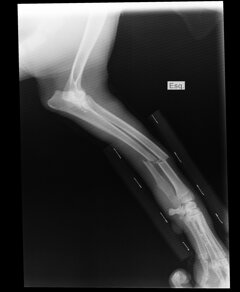

Radiologia e Radioscopia

Esame radiografico: La radiologia veterinaria usa strumenti come i raggi X, che servono a:

-Individuare corpi estranei ingeriti.

-Valutare la salute degli organi interni (cuore, polmoni, fegato, ecc.).

-Controllare la gravidanza e il numero dei cuccioli.

È uno strumento essenziale per una diagnosi precisa e per pianificare la cura migliore.